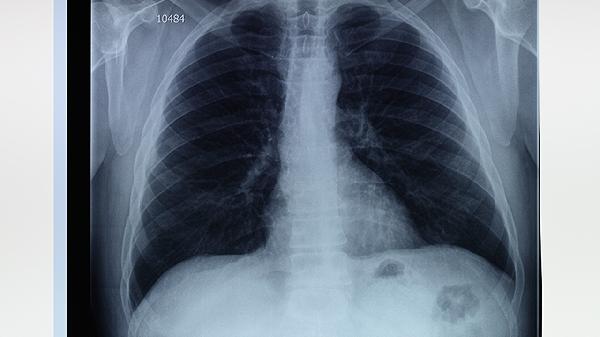

初始3个月每月复查胸部CT,观察磨玻璃样病变吸收情况。后期每6个月进行低剂量CT筛查,重点关注原有挫伤部位是否出现纤维化或肺大疱。影像学检查需结合动脉血气分析评估氧合功能。